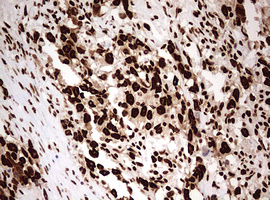

Immunohistochemical staining of paraffin-embedded Human lymphoma tissue using anti-HNRNPM mouse monoclonal antibody. (Heat-induced epitope retrieval by 10mM citric buffer, pH6.0, 120°C for 3min, M06017-2)